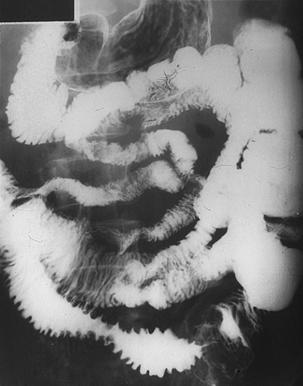

종양처럼 보이는 다발성의 소장 악성 림프종

악성 림프계종양/악성 림프종

소장/기타

X-P

40이상

다발종양(동일 장기)

유(동시성)